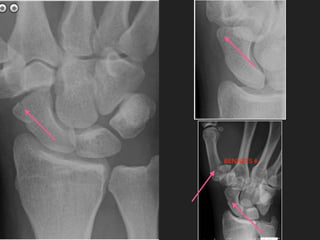

THIS IS A SCAPHO-LUNATE DISSOCIATION

▸ NOTE THE WIDE SPACE BETWEEN

THE SCAPHOID AND THE LUNATE

▸ CAUSES AN UNSTABLE WRIST

▸ VERY EASY TO MISS

▸ SEVERE PAIN ON MOVEMENT IN

THE ABSENCE OF A # SHOULD

MAKE YOU GO BACK AND

CHECK FOR THIS

FINALLY THIS IS ASCAPHO-LUNATE DISSOCIATION ▸ NOTE THE WIDE SPACE BETWEEN THE SCAPHOID AND THE LUNATE ▸ CAUSES AN UNSTABLE WRIST ▸ VERY EASY TO MISS ▸ SEVERE PAIN ON MOVEMENT IN THE ABSENCE OF A # SHOULD MAKE YOU GO BACK AND CHECK FOR THIS